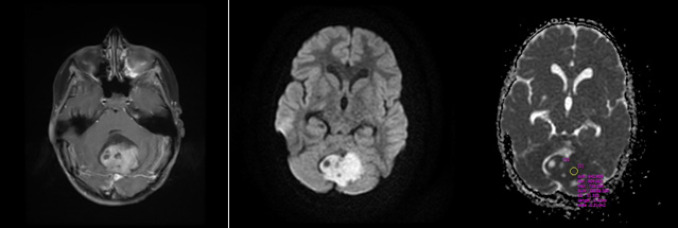

Materials & methods: This retrospective cross-sectional study was conducted on all pediatric patients with posterior fossa tumors admitted to teaching hospitals affiliated with Isfahan University of Medical Sciences from 2017 to 2022. Forty-three patients with posterior fossa tumors were identified, and seven patients were excluded due to diagnoses other than medulloblastoma or ependymoma. Tumor morphology on MRI, tumor density on CT scan, and apparent diffusion coefficient (ADC) values were assessed to differentiate medulloblastoma from ependymoma.

Results: Histopathologic diagnosis was medulloblastoma in 21 patients (60%) and ependymoma in 14 patients (40%). Mean ADC values in medulloblastoma and ependymoma cases were 0.67±0.19 (range= 0.50-1.25) and 1.22±0.29 (range=0.67-1.72), showing a significant statistical difference between the two groups (p-value=0.000). The ADC cut-off point of 0.9825 was associated with 90% sensitivity and 92.9% specificity for differentiation of ependymoma from medulloblastoma.

Conclusion: While tumor morphology on MRI and other studied parameters are unreliable for differentiating medulloblastoma and ependymoma, ADC values may provide a potential diagnostic tool. Further studies are needed to confirm the utility of DWI and other advanced MRI techniques in differentiating these tumors.